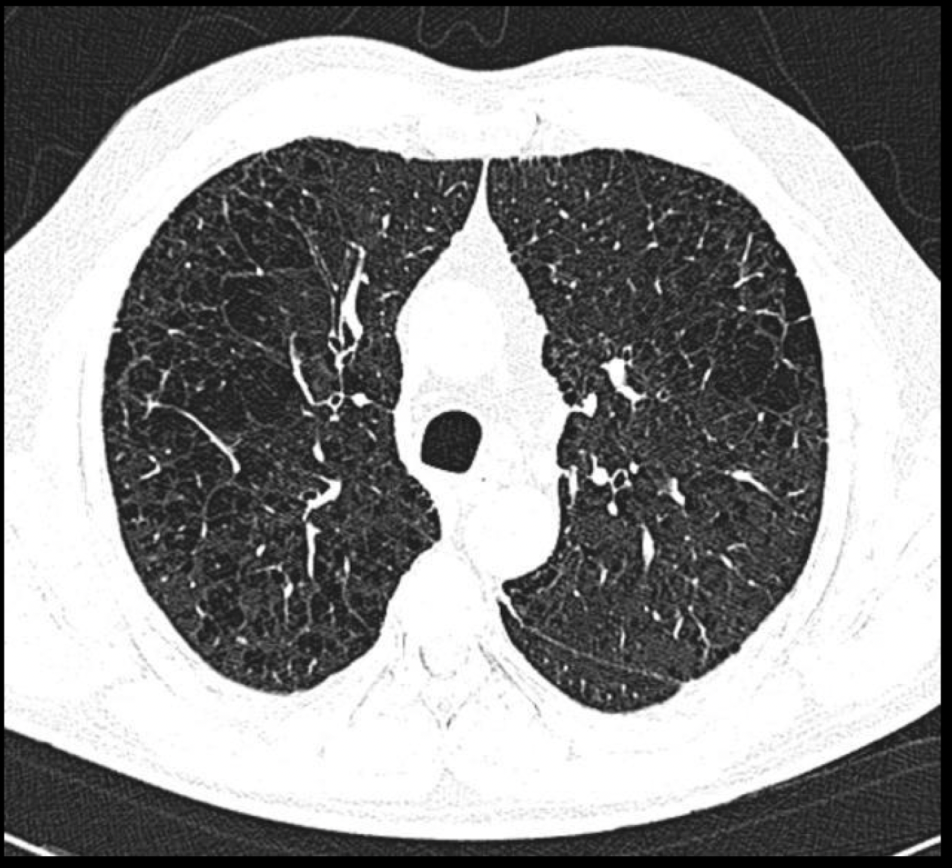

Q

Patrón que podemos ver

A

Centrolobulillar